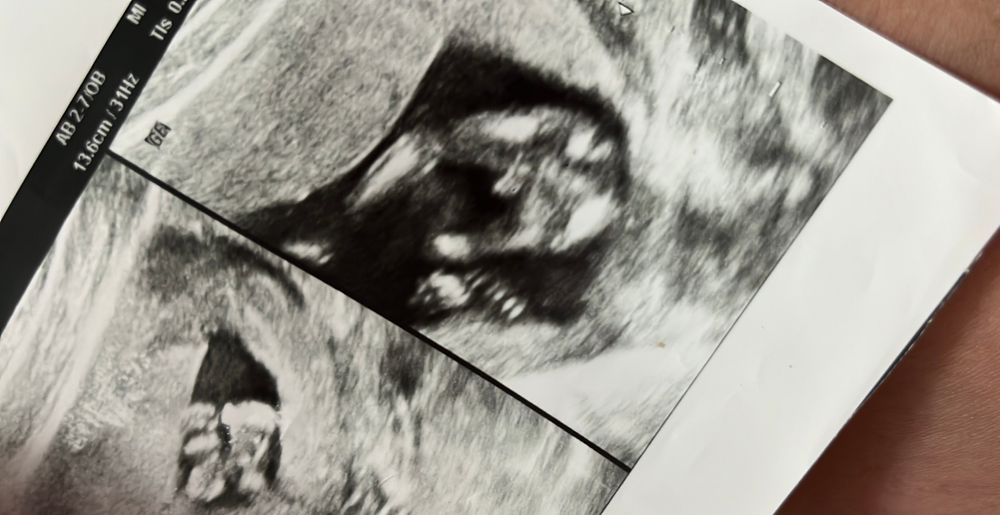

Мальчик выглядит так😀 Изображение

13.06.2024